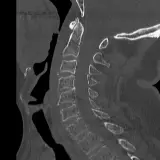

PACS์—์„œ ๊ธฐ๋Œ€ํ•  ์ˆ˜ ์žˆ๋Š” ๋ชจ๋“  ๋„๊ตฌ๋ฅผ ๊ฐ–์ถ˜ ์™„์ „ํ•œ ์ธํ„ฐ๋ž™ํ‹ฐ๋ธŒ ์ฆ๋ก€ — ์Šคํฌ๋กค, ์œˆ๋„์šฐ ์กฐ์ ˆ, ํ™•๋Œ€/์ถ•์†Œ, ํŒจ๋‹, ๊ณ„์ธก, ROI, ์ „์ฒด ํ™”๋ฉด ๋ชจ๋“œ๊นŒ์ง€ ์ง€์›ํ•ฉ๋‹ˆ๋‹ค.

์‹ค์ œ PACS ์›Œํฌ์Šคํ…Œ์ด์…˜์ฒ˜๋Ÿผ ์Šคํฌ๋กค, ํŒจ๋‹, ์œˆ๋„์šฐ ์กฐ์ ˆ, ํ™•๋Œ€/์ถ•์†Œ๊ฐ€ ๊ฐ€๋Šฅํ•ฉ๋‹ˆ๋‹ค